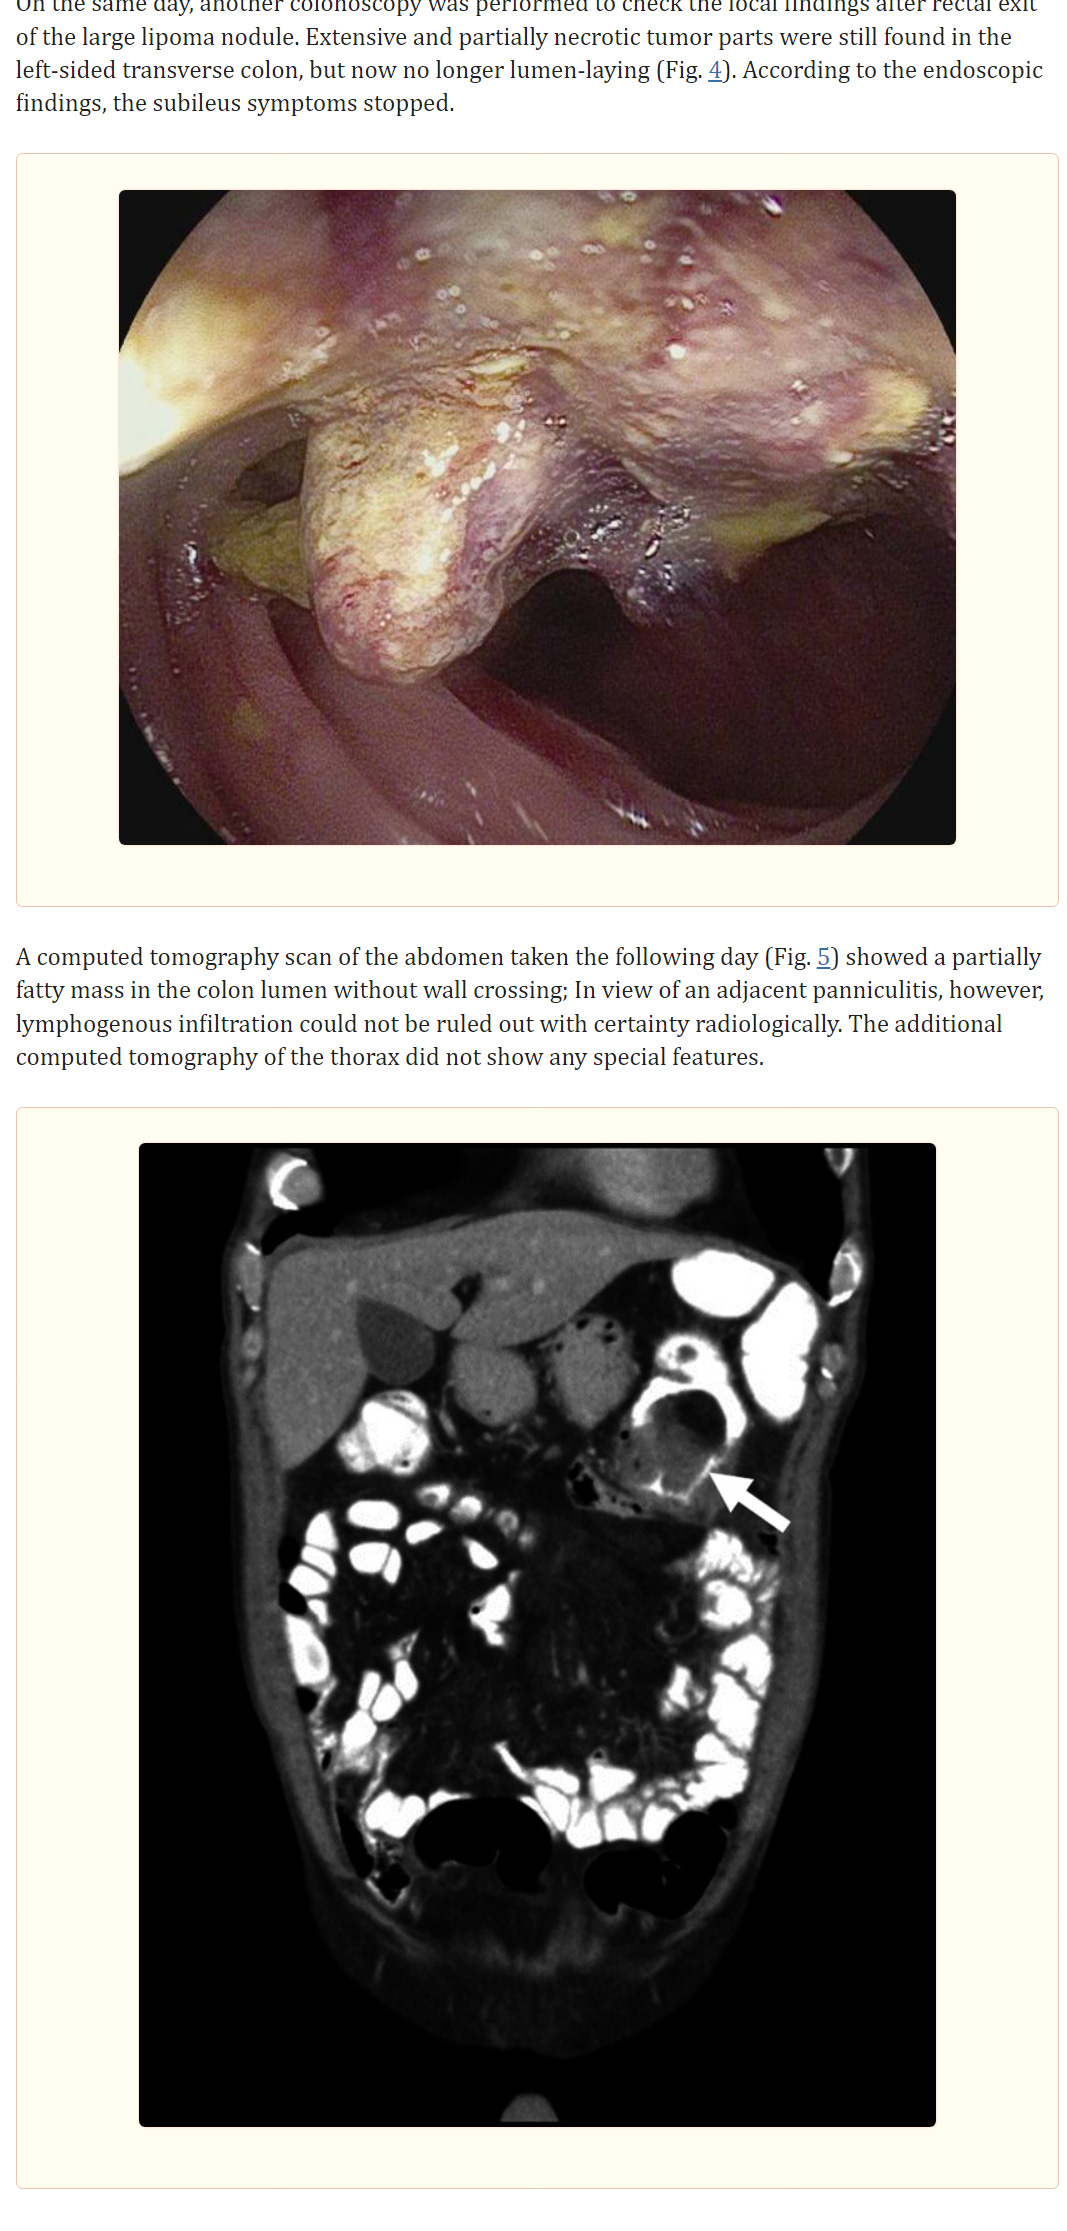

Four days after the colonoscopy, there was a spontaneous discharge of a 4.1 × 3.5 × 2.8 cm tumor nodule in the stool, histologically corresponding to a submucosal lipoma. Surgery confirmed a benign lipoma with limitation to the submucosa. Extremely rarely, a tumor node is excreted in the stool.